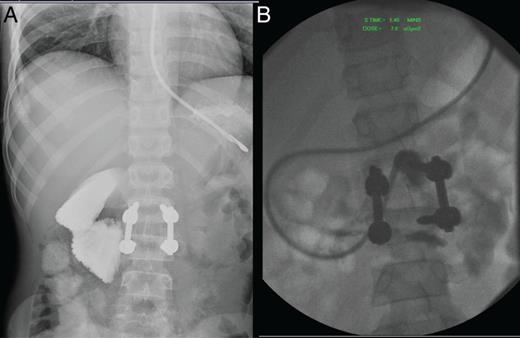

Initially he progressed well tolerating per oral (PO) intake. However, 10 days post-op his abdominal pain and nausea returned. Repeat imaging suggested a partial bowel obstruction and repeat laparotomy identified significant adhesions and stenosis of the previously involved segment of jejunum (Fig. 1C). He was commenced on TPN, and PO intake was slowly reduced post-operatively. His PO intake remained poor, and he continued to have ongoing intermittent abdominal pain with significant post-prandial discomfort. A barium meal and follow-through study was performed 1 week post-relaparotomy, and a diagnosis of SMA syndrome was made (Fig. 2).

(A) Barium swallow through NG demonstrating SMA syndrome with cut-off at D3. (B) Advancement of NG tube past D3 into jejunum prior to commencing feeds.

The nasogastric (NG) was advanced past the point of obstruction (now nasojejunal tube), and feeding was commenced. Since his admission, he had lost over 10 kg at this point. He was eventually tolerating PO intake and off TPN one 40 days post-admission and was transferred for rehabilitation and ongoing bowel management with regular laxatives.